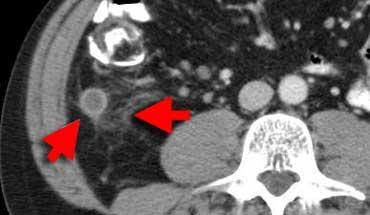

TRÁI: Viêm túi thừa sigma. Túi thừa (mũi tên) được bao quanh bởi lớp mỡ tăng tỷ trọng. Thành sigma dày. PHẢI: Ung thư sigma với dấu hiệu mờ mỡ giới hạn.